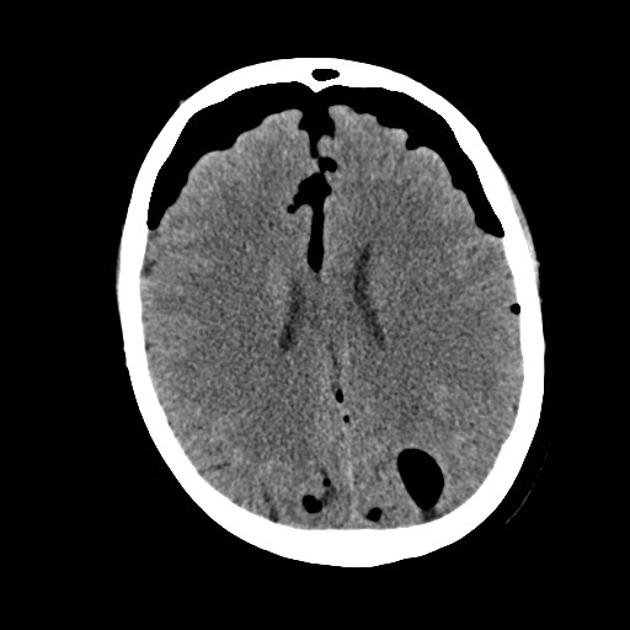

В нативном режиме определяется наличие газа в полостях черепа, чаще всего в области лобных, височных рогов боковых желудочков, супраселлярной цистерны, межполушарной щели или субдурального пространства, что свидетельствует о нарушении целостности твёрдых или мягких оболочек мозга.

В режиме сканирования мягких тканей головы выявляется отсутствие структурной деформации вещества мозга вокруг скопления газа, если объём воздуха невелик, либо компрессия и сдавление прилежащих участков при напряжённой пневмоцефалии.

- Форма и объём газовых скоплений, что позволяет оценить выраженность пневмоцефалии и её потенциальную компрессию на структуры головного мозга.

- Степень компрессии мозга или желудочковой системы при напряжённой форме пневмоцефалии, что важно для определения показаний к срочной хирургической помощи.